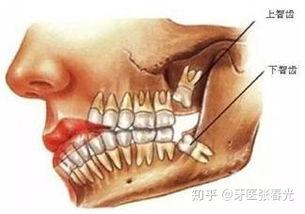

智齿的形态与分布

智齿,又称为第三磨牙,位于口腔最里面的位置。它通常在18岁到25岁之间长出,但也有的人可能一辈子都不会长出智齿。智齿的形态各异,有的长得整齐,有的却长得歪歪扭扭。而且,智齿的分布也很有趣,有的人长出一颗,有的人长出两颗,甚至有的人长出三颗。